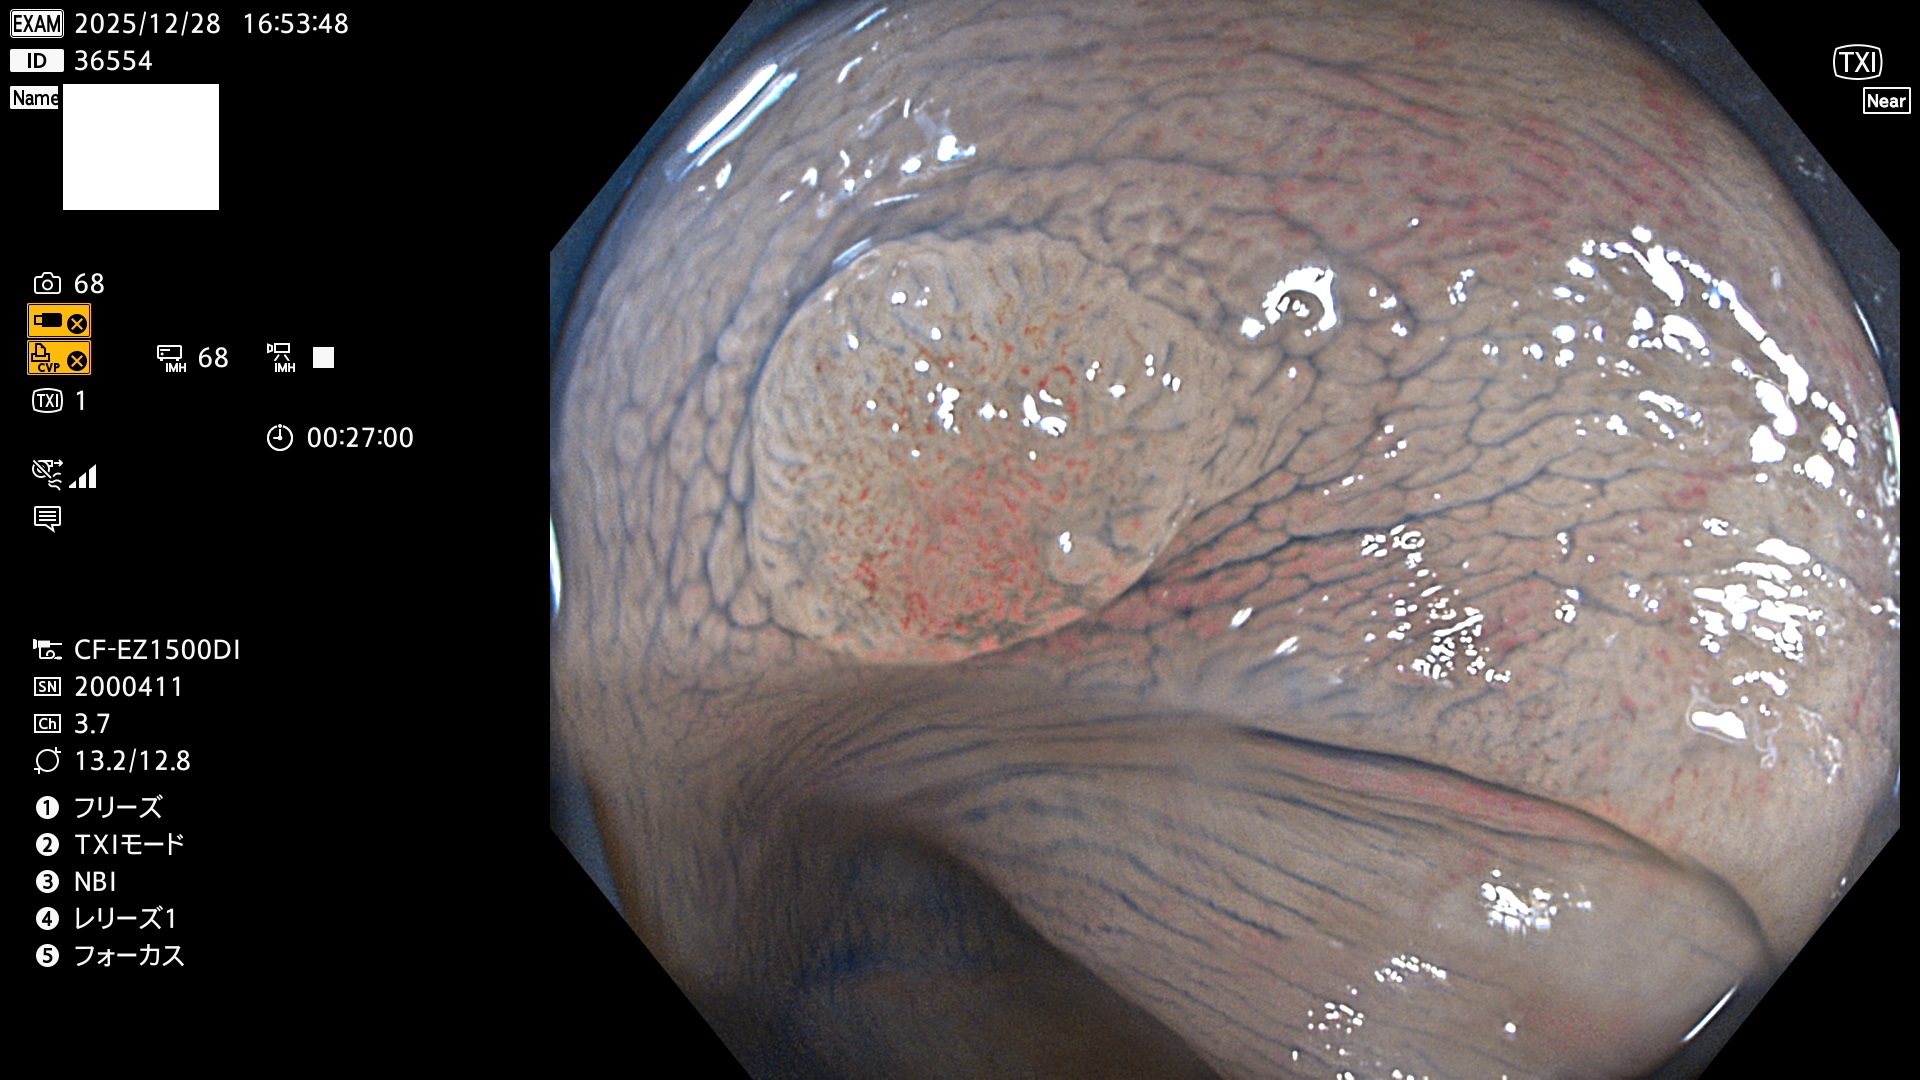

完全に平坦な物をUb、陥凹している物をUcと呼びます。Ubは認識が困難で、Ucはびらん(炎症)と紛らわしいために見落とされやすく、「内視鏡後・大腸癌」の原因になります。

毎週の検査(木・金・土・日)に発見されたUbとUc型・腺腫を、その週の日曜の夜にUPし1週間、提示します。

2025年12月18日〜12月29日の8日間(80件)13個 (Uc_ADR=13個/80人=16%)